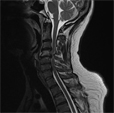

Mielopatia

cervicale |